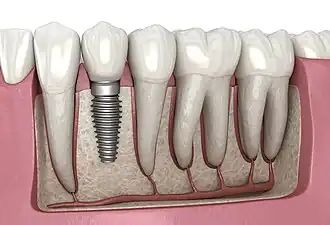

A dental implant (also known as an endosseous implant or fixture) is a prosthesis that interfaces with the bone of the jaw or skull to support a dental prosthesis such as a crown, bridge, denture, or facial prosthesis or to act as an orthodontic anchor. The basis for modern dental implants is a biological process called osseointegration, in which materials such as titanium or zirconia form an intimate bond to the bone.[1] The implant fixture is first placed so that it is likely to osseointegrate, then a dental prosthetic is added. A variable amount of healing time is required for osseointegration before either the dental prosthetic (a tooth, bridge, or denture) is attached to the implant or an abutment is placed which will hold a dental prosthetic or crown.

Single tooth implant restoration

Single tooth restorations are individual freestanding units not connected to other teeth or implants, used to replace missing individual teeth.[10] For individual tooth replacement, an implant abutment is first secured to the implant with an abutment screw. A crown (the dental prosthesis) is then connected to the abutment with dental cement, a small screw, or fused with the abutment as one piece during fabrication.[14]: 211–232 Dental implants, in the same way, can also be used to retain a multiple tooth dental prosthesis either in the form of a fixed bridge or removable dentures.